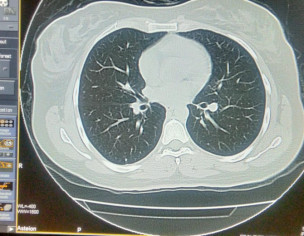

Asking for Sister, Female, 33 years old, Isl

Plz describe it. Film of hrct of corona patient

plz contact radiologist

Send full films, its incomplete